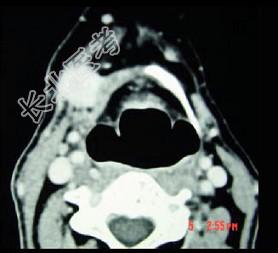

- 单项选择题男,45岁, 右侧颌下扪及一包块约4个月,无痛, PE:包块质硬, 表面欠光整,移动度较差, CT如图所示,最可能诊断为 ( )